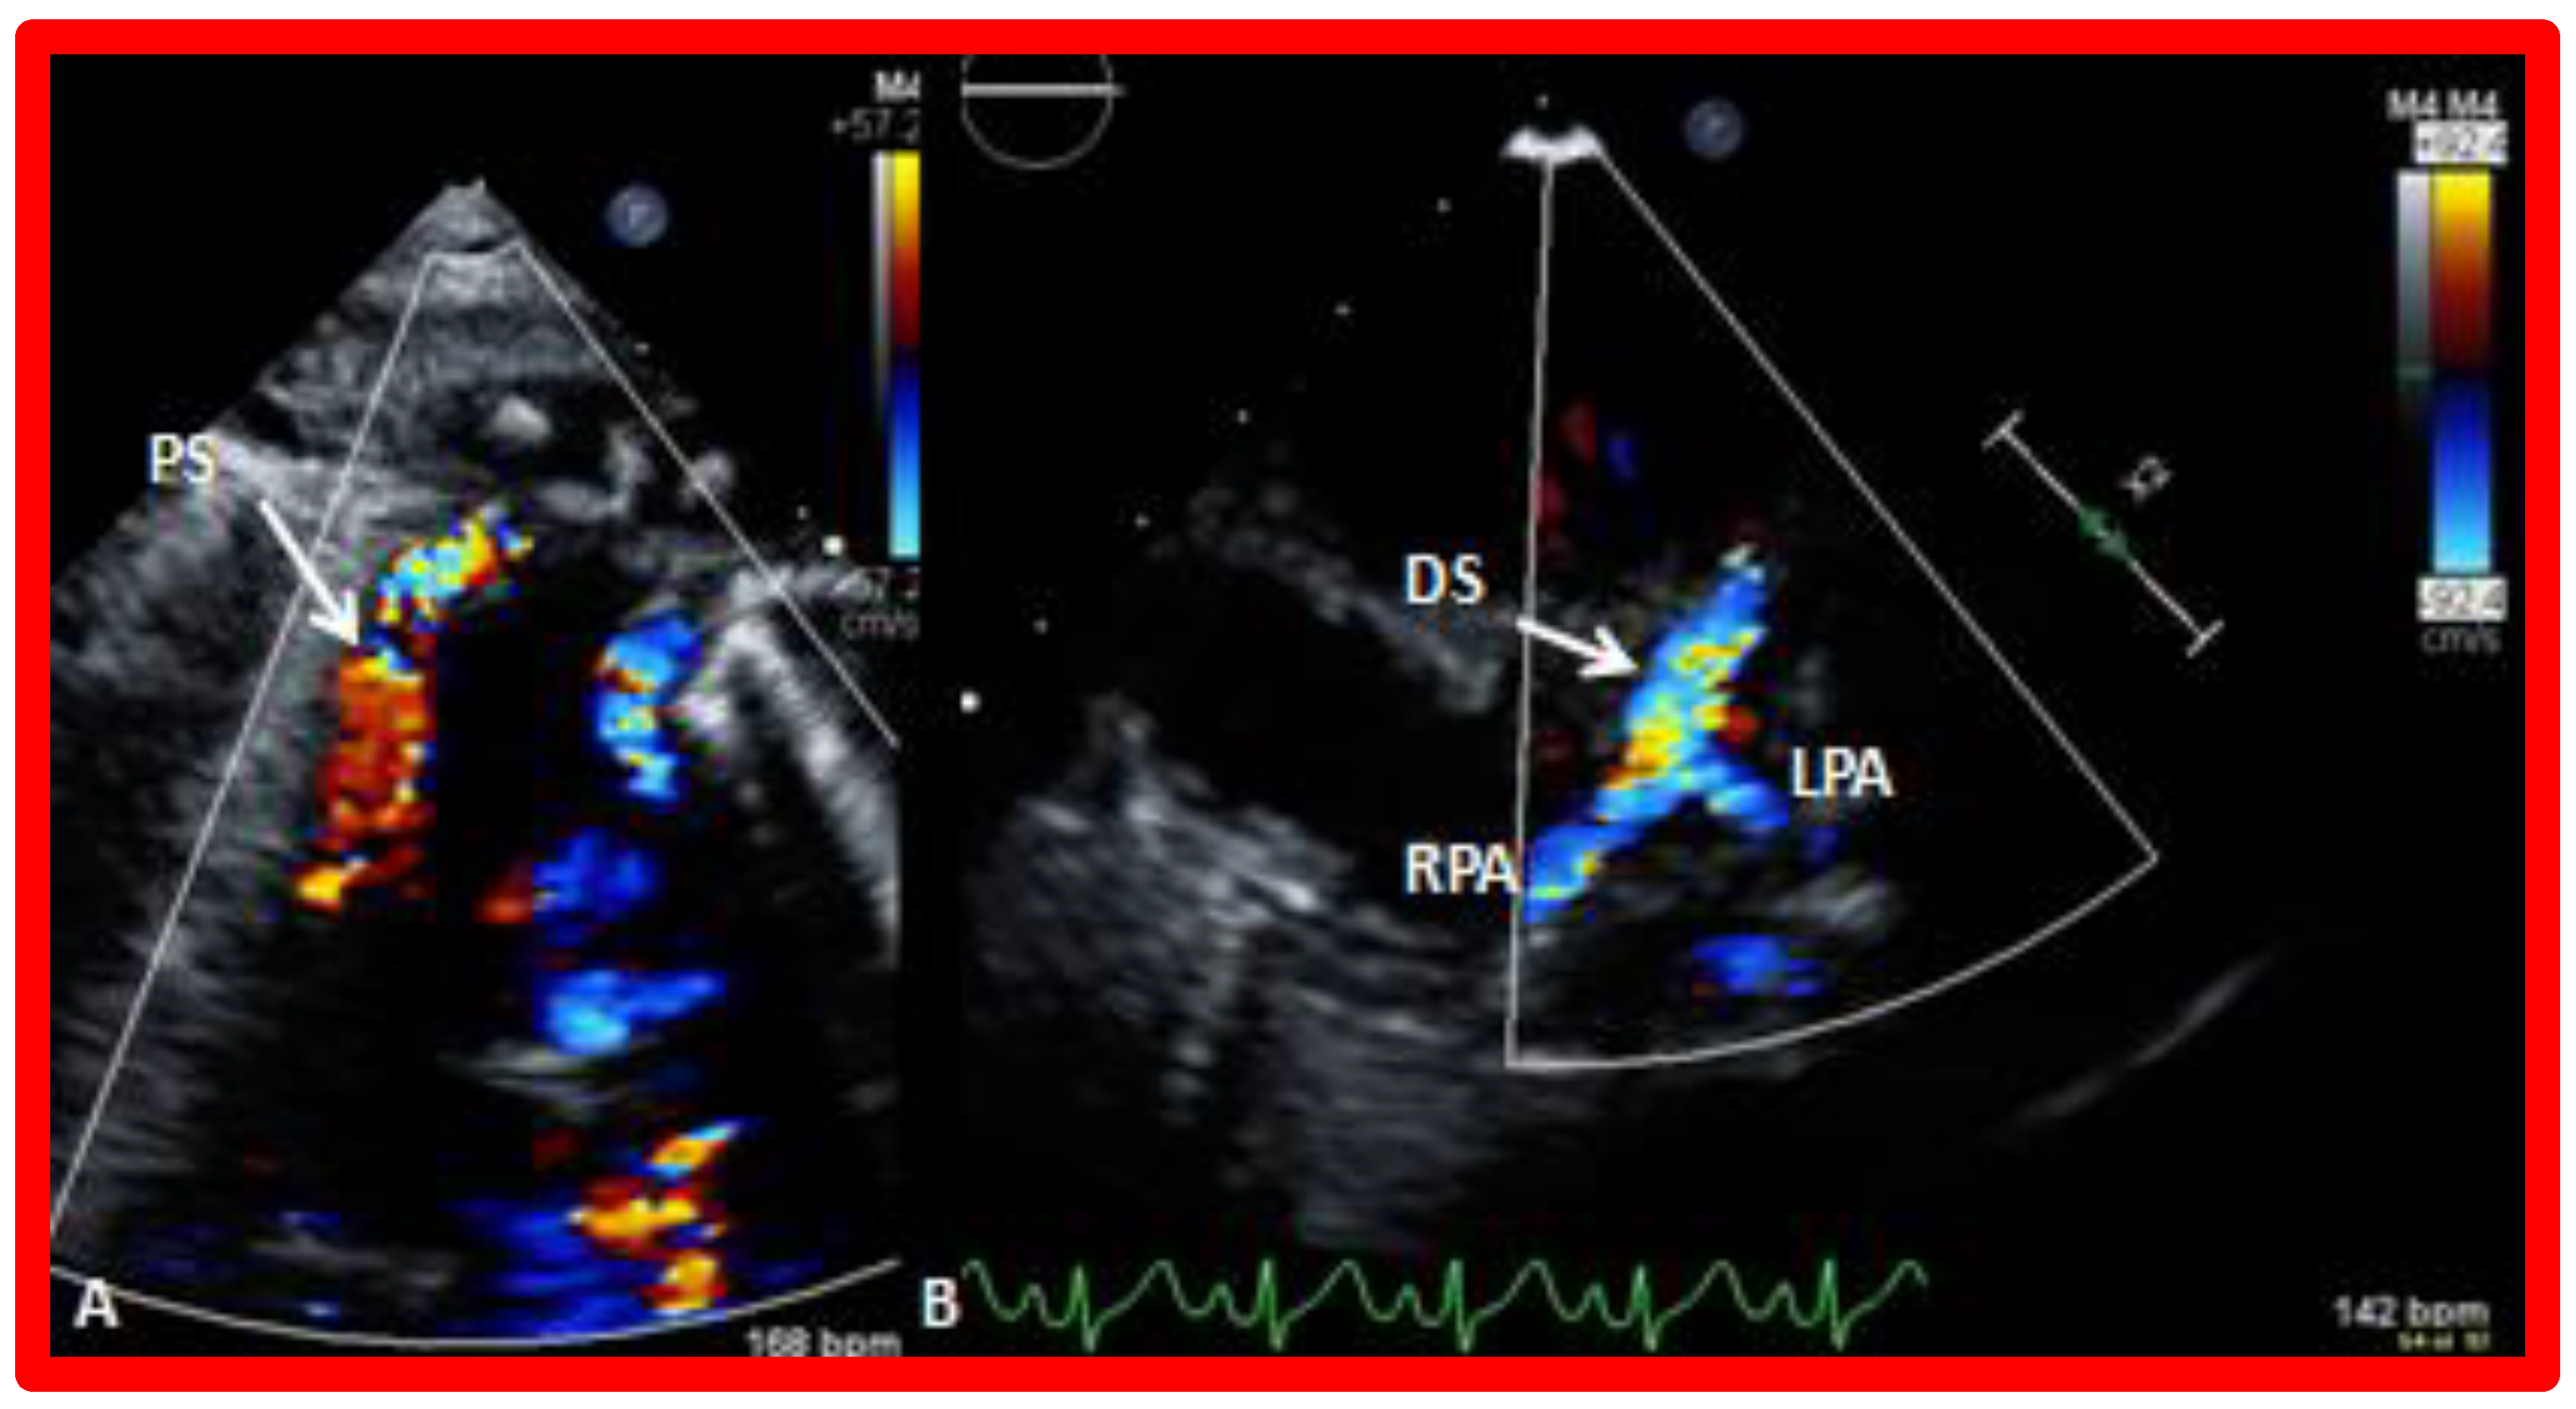

8. Echocardiogram